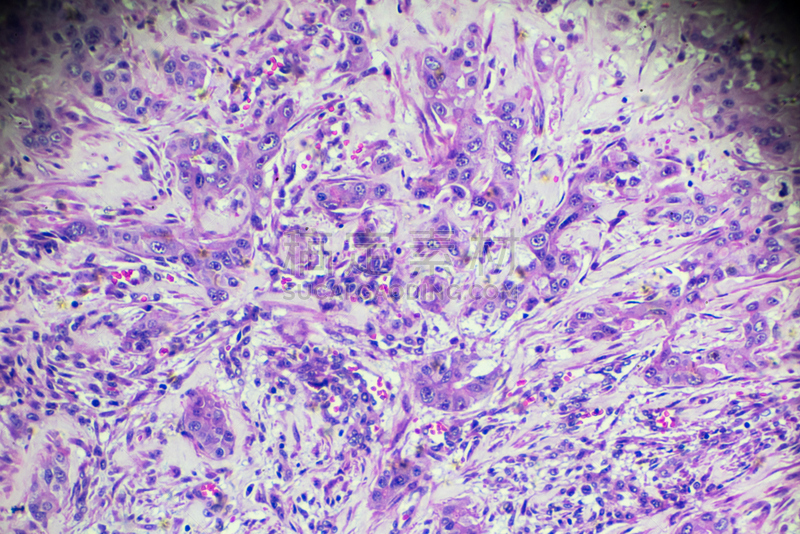

详情

JPG